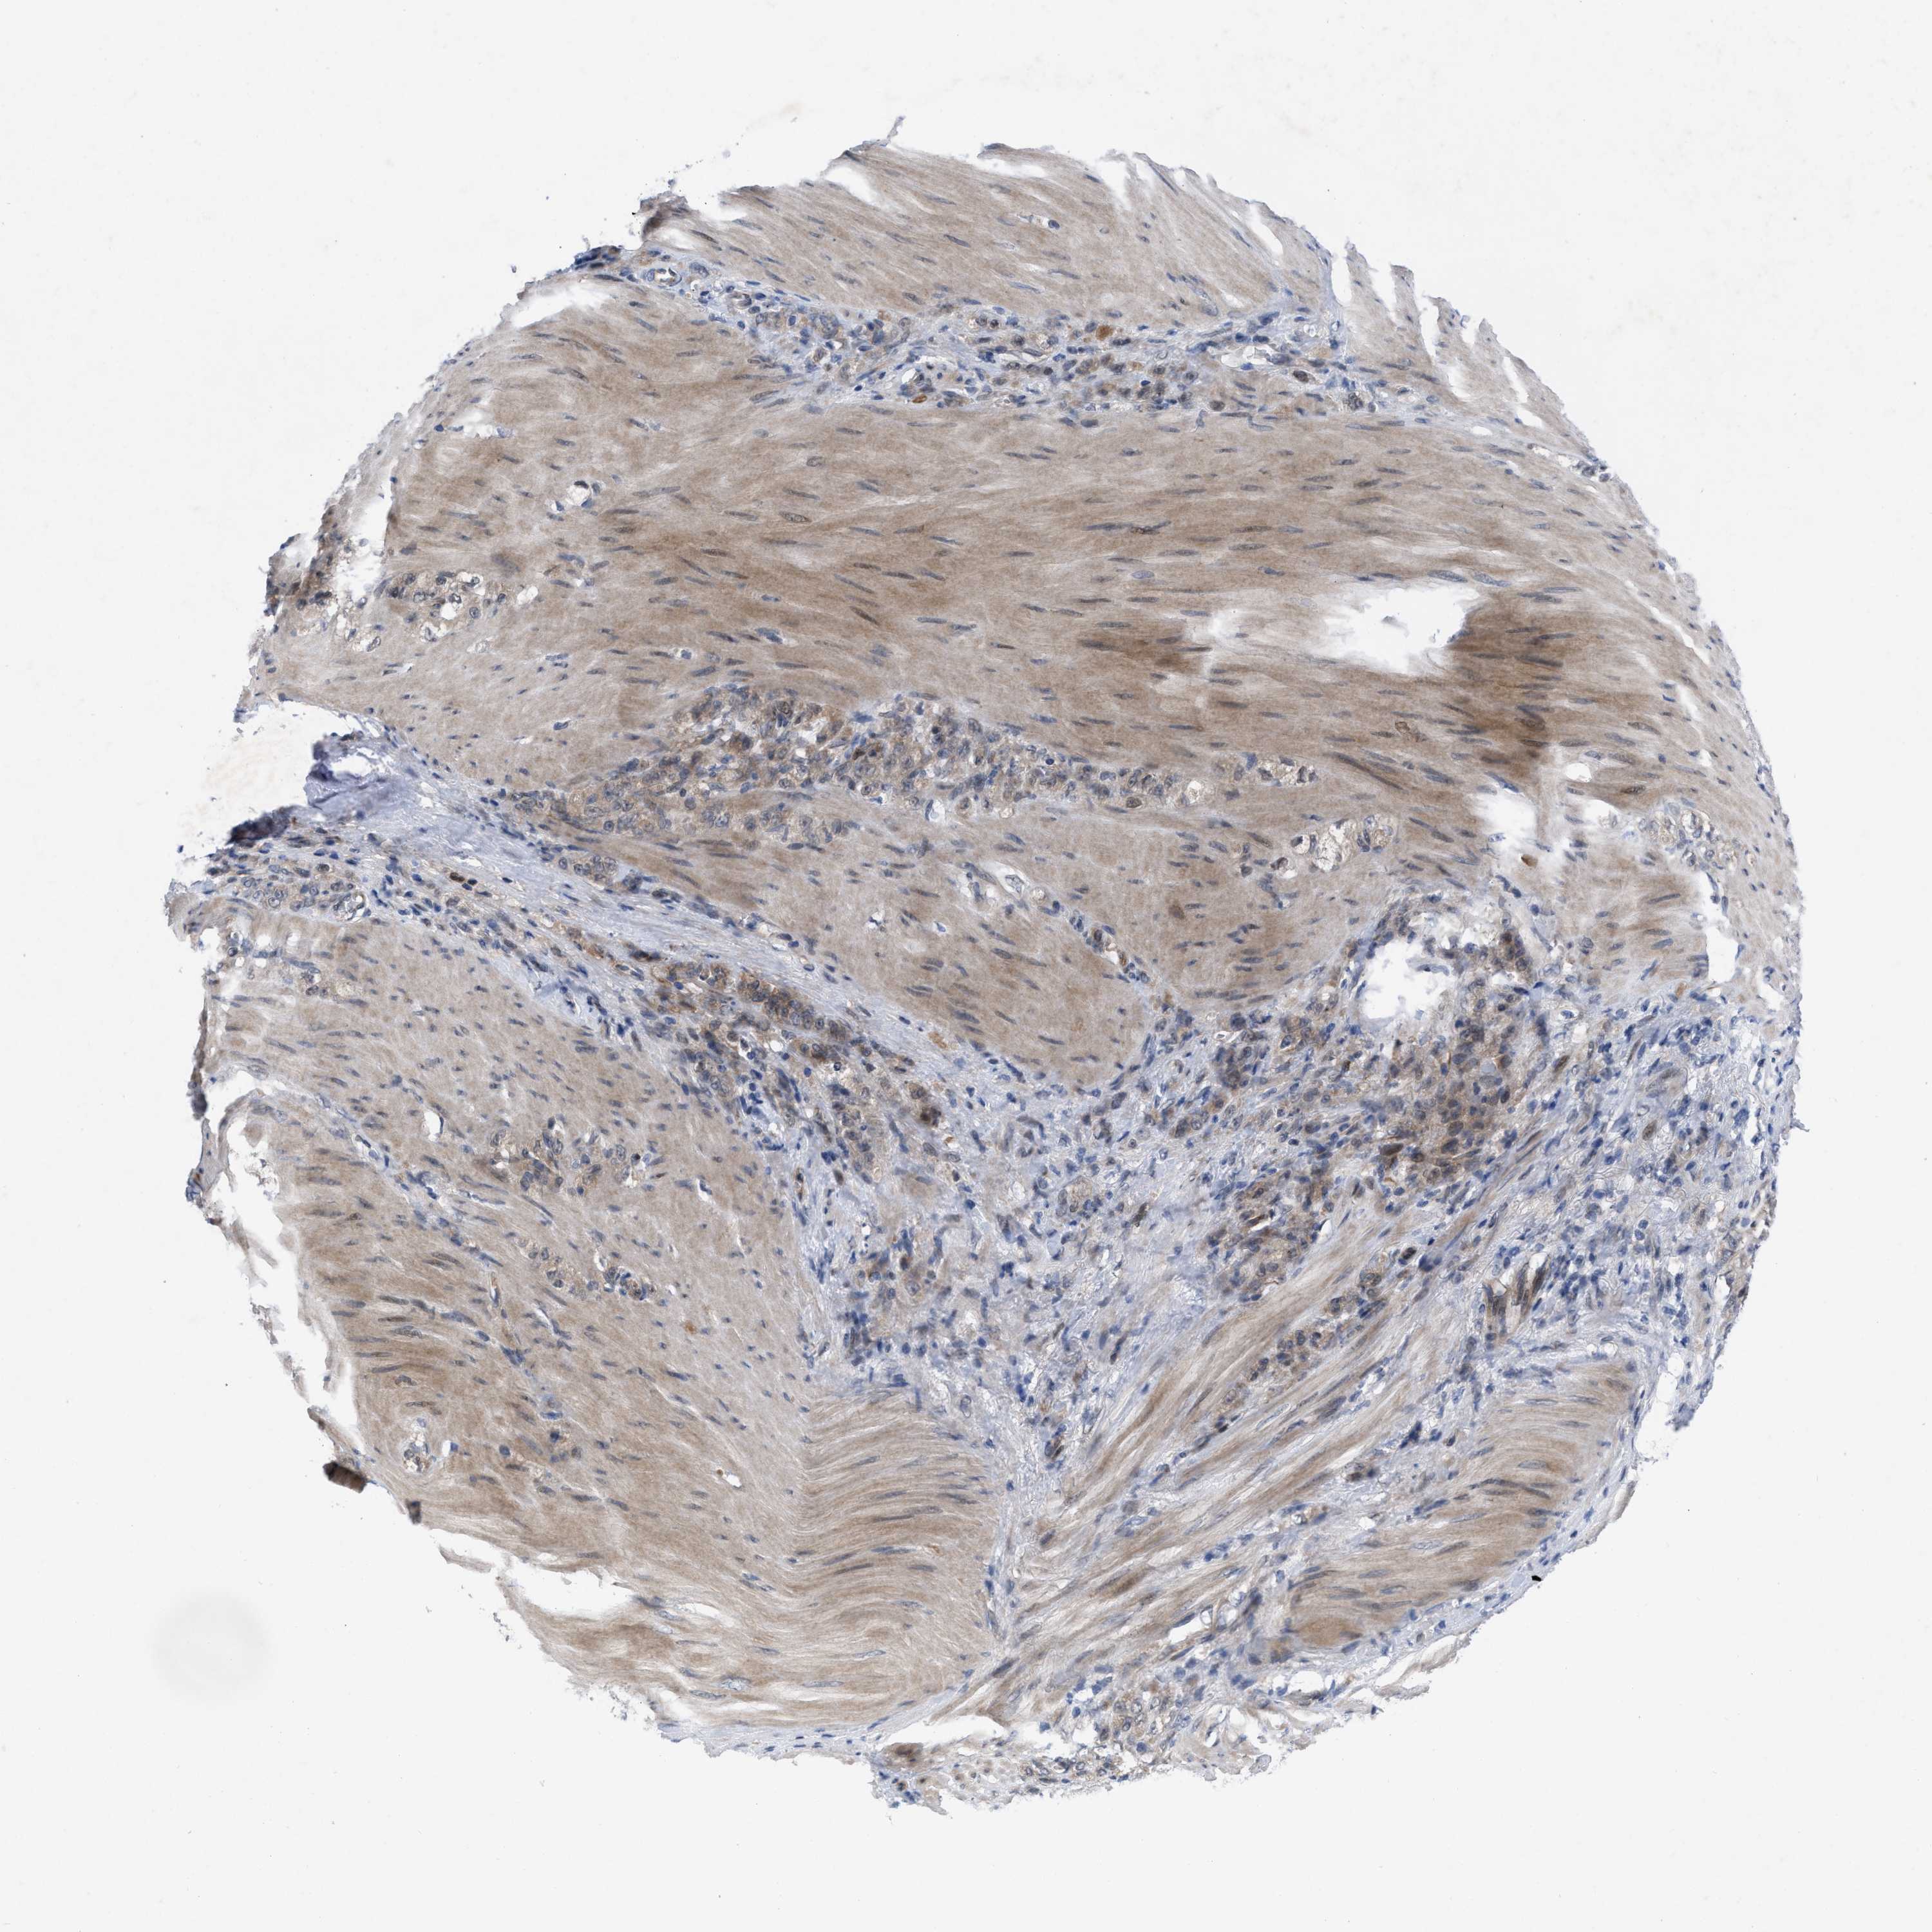

STOMACH CANCER - Protein expressioni

A mouse-over function shows sample information and annotation data. Click on an image to view it in a full screen mode. Samples can be filtered based on level of antibody staining by selecting one or several of the following categories: high, medium, low and not detected. The assay and annotation is described here.

Note that samples used for immunohistochemistry by the Human Protein Atlas do not correspond to samples in the TCGA dataset.

Antibody stainingi

Antibody staining in the annotated cell types in the current human tissue is reported as not detected, low, medium, or high, based on conventional immunohistochemistry profiling in selected tissues. This score is based on the combination of the staining intensity and fraction of stained cells.

Each image is clickable and will lead to virtual microscopy that enables deeper exploration of all samples and also displays staining intensity scores, fraction scores and subcellular localization as well as patient and tissue information for each sample.

Antibody HPA019011

Staining

High

Medium

Low

Not detected

Intensity

Strong

Moderate

Weak

Negative

Quantity

>75%

75%-25%

<25%

None

Location

Nuclear

Cytoplasmic/membranous

Cytoplasmic/membranous,nuclear

Adenocarcinoma, NOS